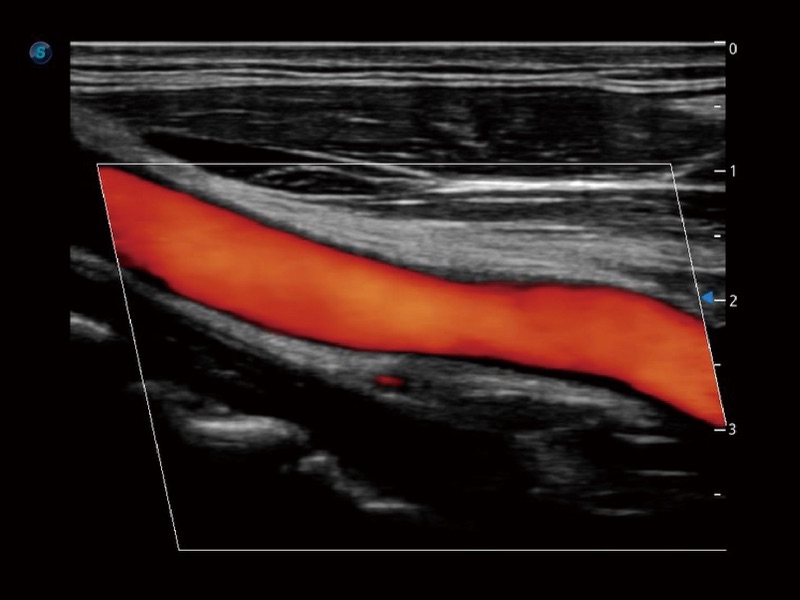

小器官应用

血管内中膜的厚度值是预测心血管疾病风险的重要指标,Auto IMT可以实现血管近场和远场内中膜厚度的自动测量,为临床提供快捷有效的诊断工具。